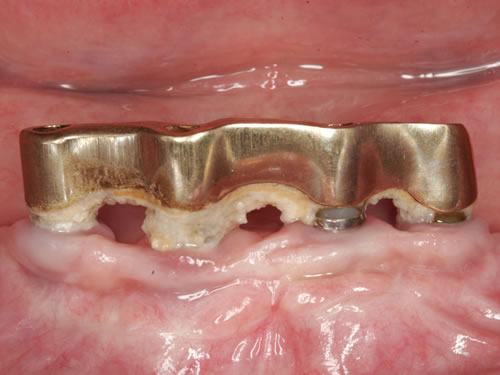

Diese Beispiele ließen sich endlos fortführen. Sie zeigen die Probleme bei der Versorgung zahnloser Kiefer, wie sie immer wieder geschildert werden. Mit Hilfe sehr einfacher Maßnahmen kann durch die Einpflanzung künstlicher Zahnwurzeln eine instabile Prothese soweit befestigt werden, dass die Kau- und Sprechfunktion wieder hergestellt ist. Manchmal kann die alte Prothese weiterverwendet werden, in dem man in die Prothesenbasis Sekundärteile einarbeitet, die für Halt sorgen (Abb. 3.5, 3.6). Bei aufwendigeren Steg- oder Teleskoparbeiten muss auch der Zahnersatz der auf den Implantaten fixiert wird neu angefertigt werden. Diese Arbeiten werden dann brückenartig und sehr grazil gestaltet. (Abb. 3.7 bis 3.12).

Abb. 3.8: Individuelle Stegversorgung aus Gold auf vier Implantaten im zahnlosen Unterkiefer.

Für den zahnlosen Ober- und Unterkiefer werden dies häufiger Stegkonstruktionen oder Teleskopversorgungen sein (Abb. 8.8 bis 8.16).

Abb. 8.8: Individueller Steg auf 4 Implantaten im zahnlosen Unterkiefer.